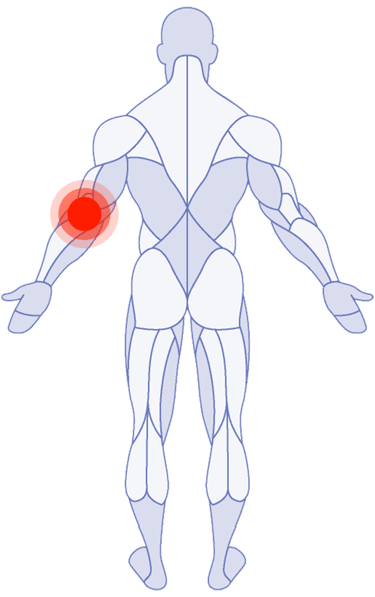

Shoulder Pain

Tricep Pain

Where Do You Need Attention?

Use the latest research in physical therapy to work better, play better and spend more time on what really matters.